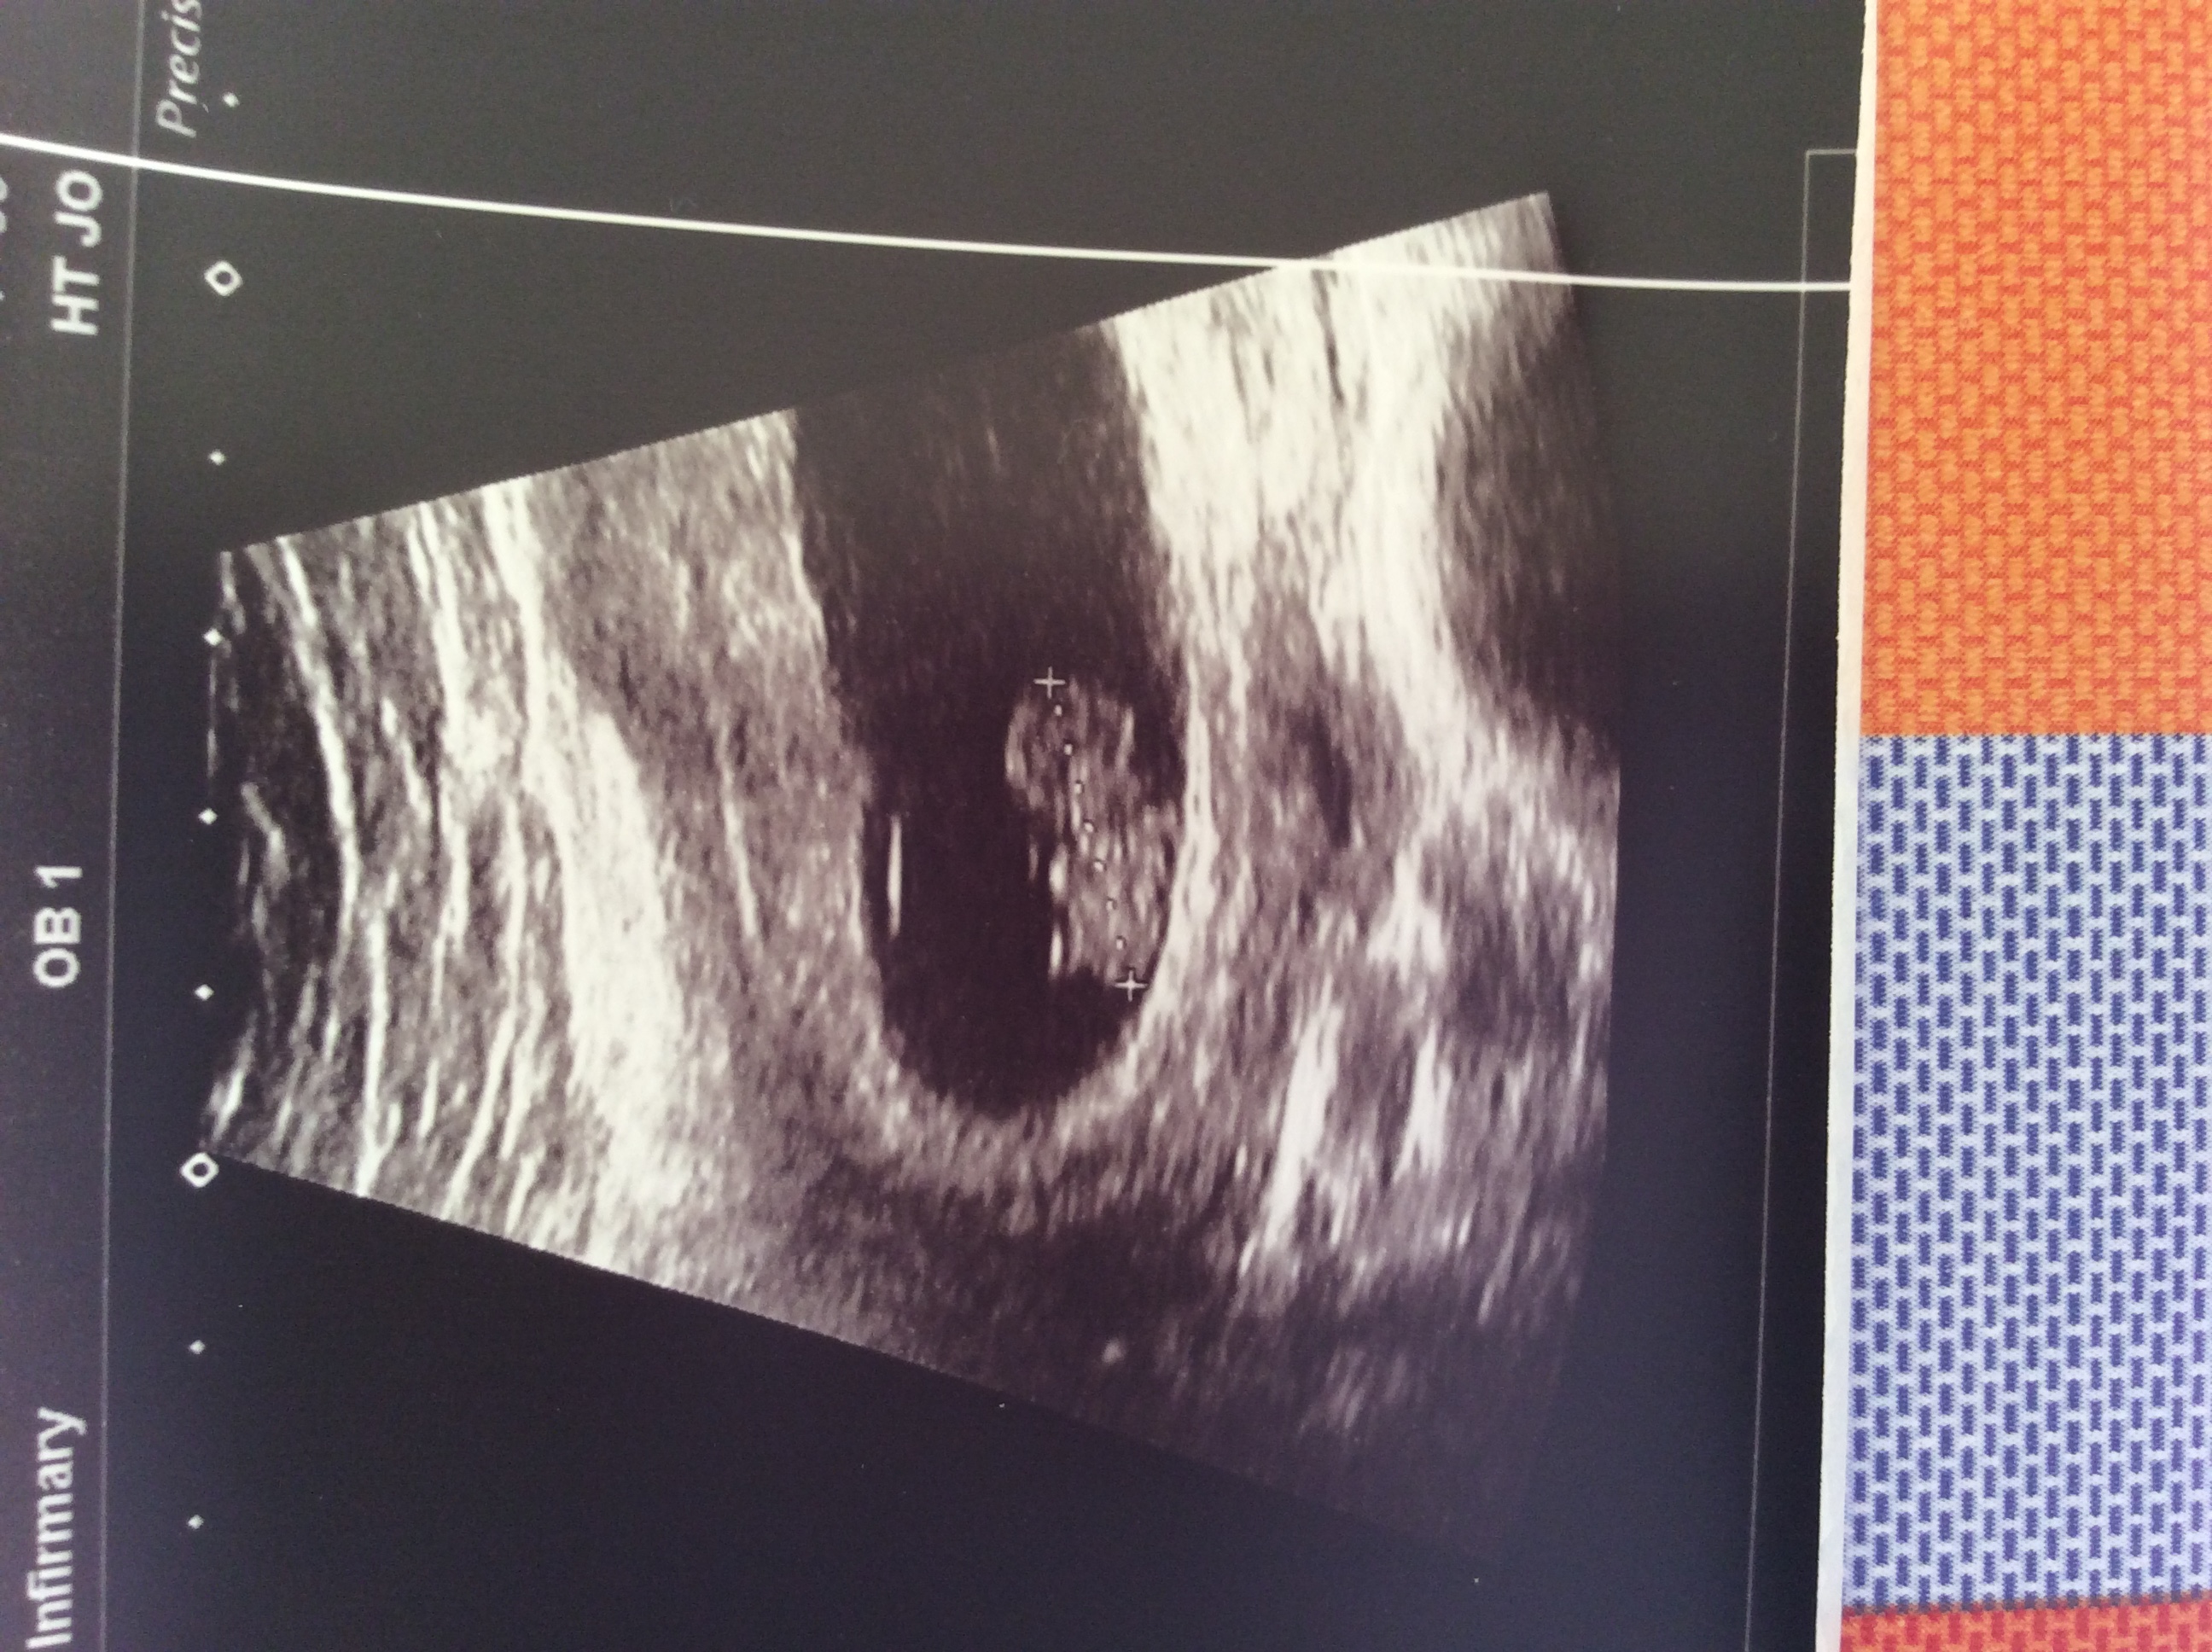

The above is the 6 week scan, the one below in the 8 week scan. Both have the measurement marker shown on the baby. On the 6 weeks scan, the pole and sac (I think ) is the blob to the right of the baby. Attachment 31487